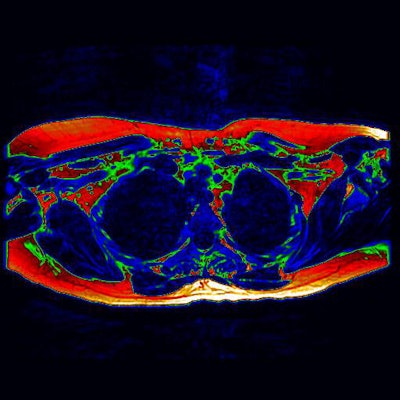

As a critical step toward new therapies to aid the fight against diabetes and obesity, British researchers for the first time are using MRI to show the presence of brown adipose tissue in a living adult.

A new study from Warwick Medical School and University Hospitals Coventry and Warwickshire National Health Service (NHS) Trust, published in the Journal of Clinical Endocrinology and Metabolism (January 2014, Vol. 99:1, pp. E117–E121), outlines the benefits of MRI instead of PET to better detect and visualize so-called brown fat.

Unlike PET data, which only displays activity, MRI shows brown fat content whether active or not to provide detailed insight into where it can be found in the adult body. This information could prove vital in the creation of future therapies that seek to activate deposits of brown fat.